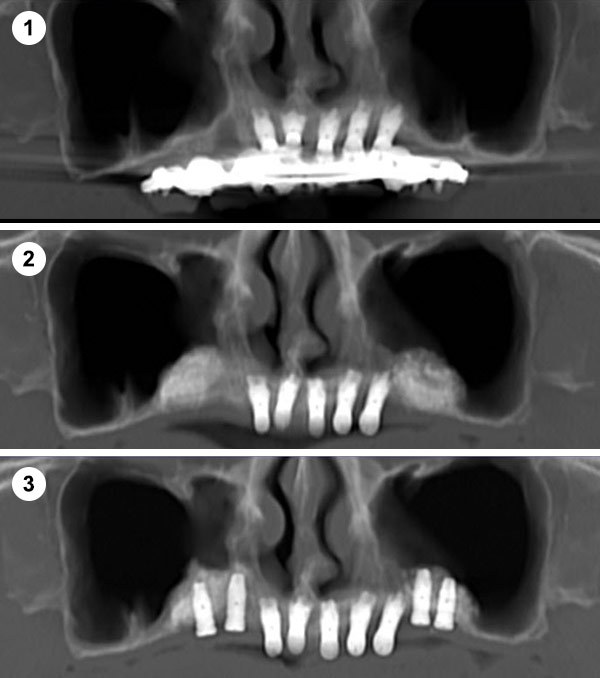

¿Qué es la Elevación Traumática?

Se realiza a través de una apertura lateral en la pared del seno maxilar (ventana lateral). Este enfoque permite un acceso directo a la membrana sinusal para su elevación.

Indicaciones: Se emplea en casos donde la cantidad de hueso residual es muy escasa (<5 mm) o cuando se necesita un aumento significativo del volumen óseo.

Permite una visualización directa y control del procedimiento. Útil para grandes reconstrucciones óseas.

¿Qué es la Elevación Atraumática?

Se realiza a través de la misma osteotomía de colocación del implante, utilizando fresas o dispositivos especiales para levantar la membrana sinusal de manera indirecta.

Indicaciones: Se recomienda cuando existe una altura de hueso residual moderada (alrededor de 5-8 mm) y el aumento necesario no es muy grande.

Es menos invasiva, con una recuperación más rápida y menor riesgo de complicaciones y molestias postoperatorias.